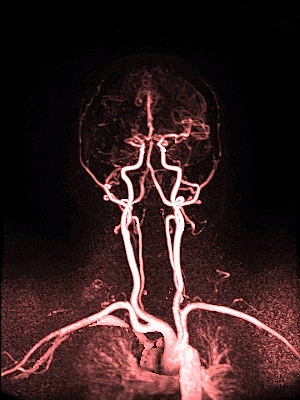

MRA collateral map: ‘DeepClue-Precise MR 측부혈류영상'

MR 혈관영상을 이용한 측부혈류영상

동맥기

모세혈관기

조기정맥기

후기정맥기

지연기